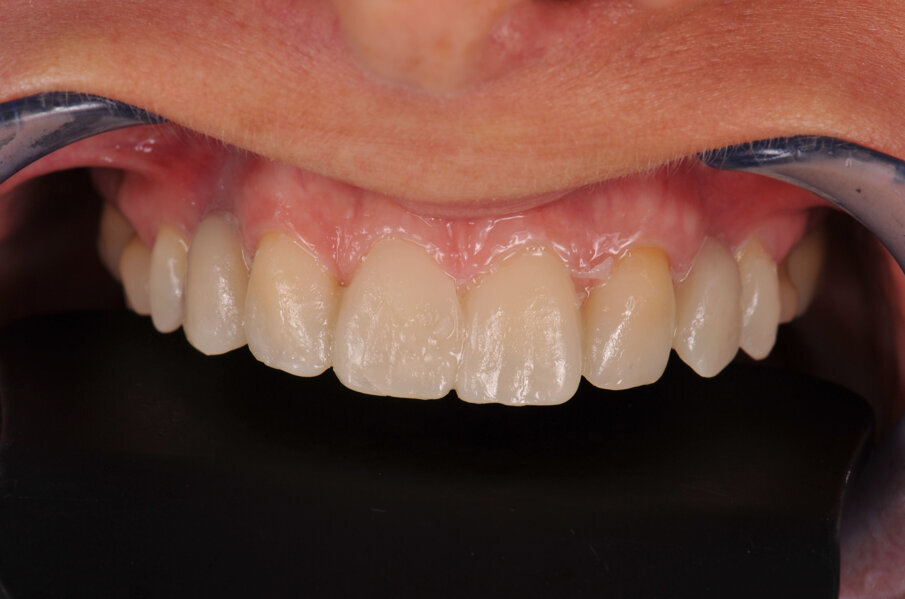

Om de behandeling niet nodeloos ingewikkeld te maken, is een set-up gemaakt waarin is gekeken of we met een restauratief/orthodontisch behandelplan uit de voeten kunnen om zo orthognatische chirurgie te vermijden. Er werd een wax-up gemaakt en deze werd met Luxatemp gepast bij de patiënte om te beoordelen of we dimensionaal goed zouden uitkomen. Deze mock-up werd ook gemaakt om patiënte te laten zien welk uiteindelijk esthetisch resultaat we zouden kunnen benaderen (afbeelding 3 en 4).